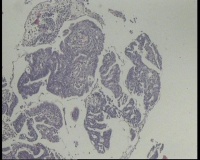

镜下见子宫内膜腺体异型增生,呈乳头状,筛网状排列,细胞核圆形,大小尚均匀,可见少量核分裂像,部分区域鳞化,间质少,部分区域无间质,间质有坏死